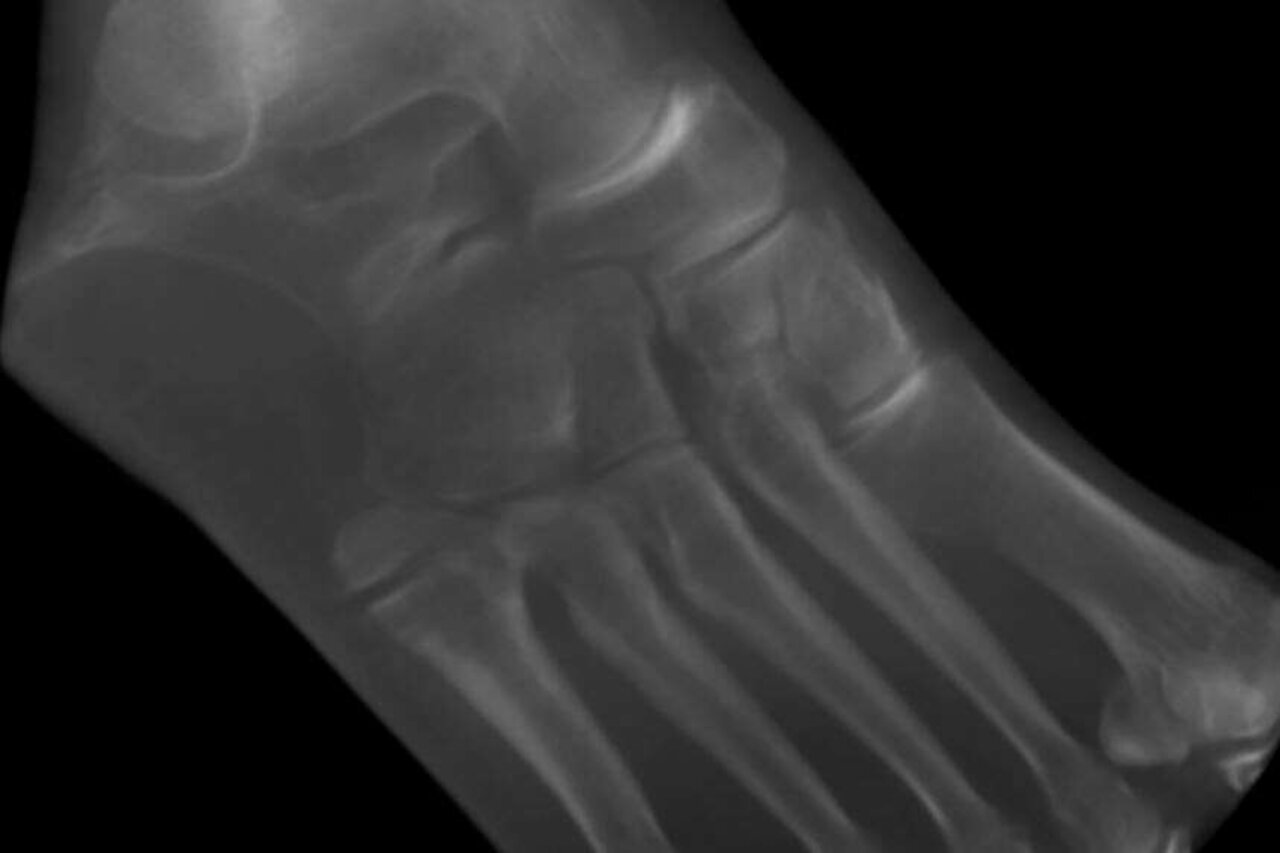

MT 5 Basisfraktur mit Pseudarthrose